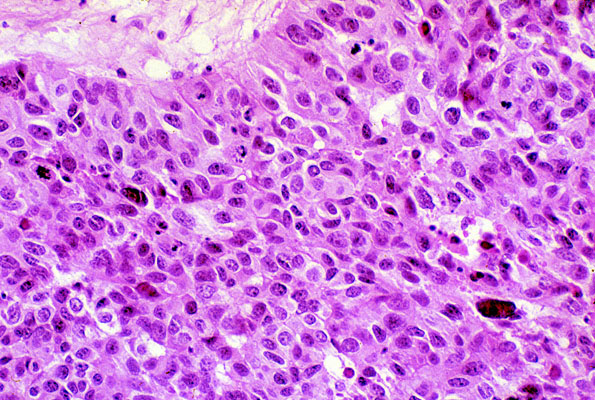

Transitional cell carcinoma, grade III

The tumor nests are composed of cells that show marked pleomorphism, and only vaguely resemble transitional epithelium.